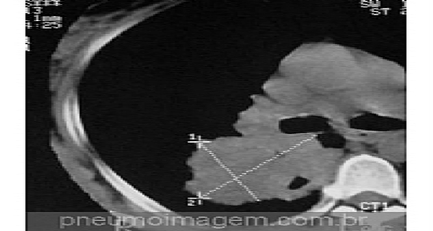

Veja imagens de câncer de pulmão não pequenas células no PneumoImagem clicando aqui.